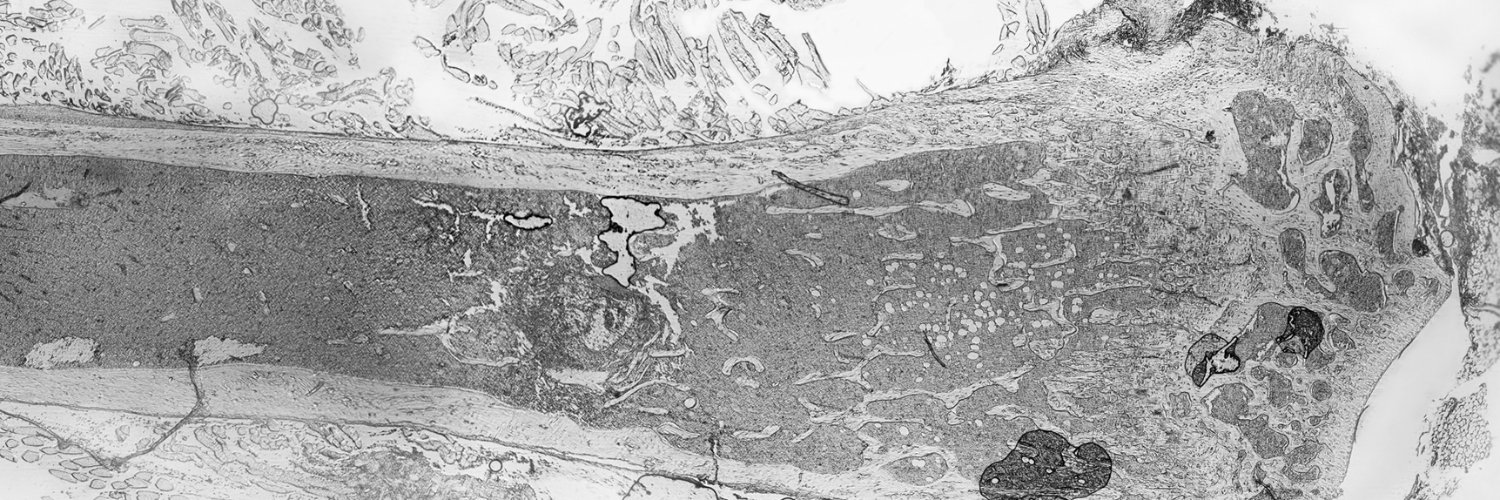

Ana Carolina Monteiro (NeSk PhD student) shared her work at yesterday’s #YoungScientistsSeminar @i3S_UPorto , developing microphysiological platforms to model tumor–nerve crosstalk in the bone microenvironment, helping bridge 𝘪𝘯 𝘷𝘪𝘵𝘳𝘰 models and clinical reality. 👏